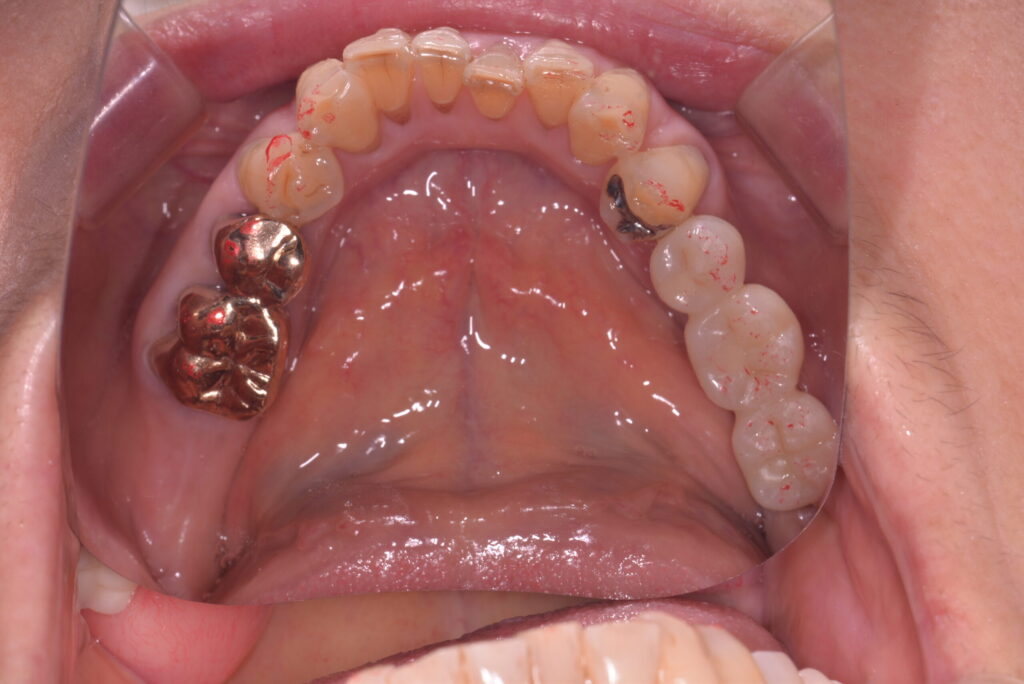

術後